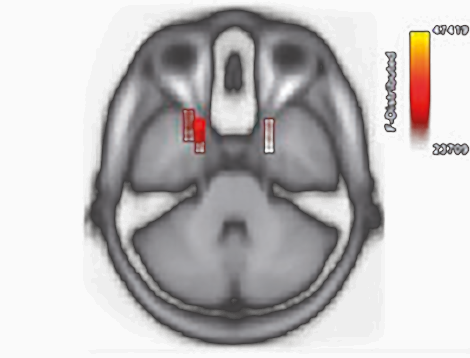

Julia Campbell and Anu Sharma, "Compenstatory changes in cortical resource in adults with